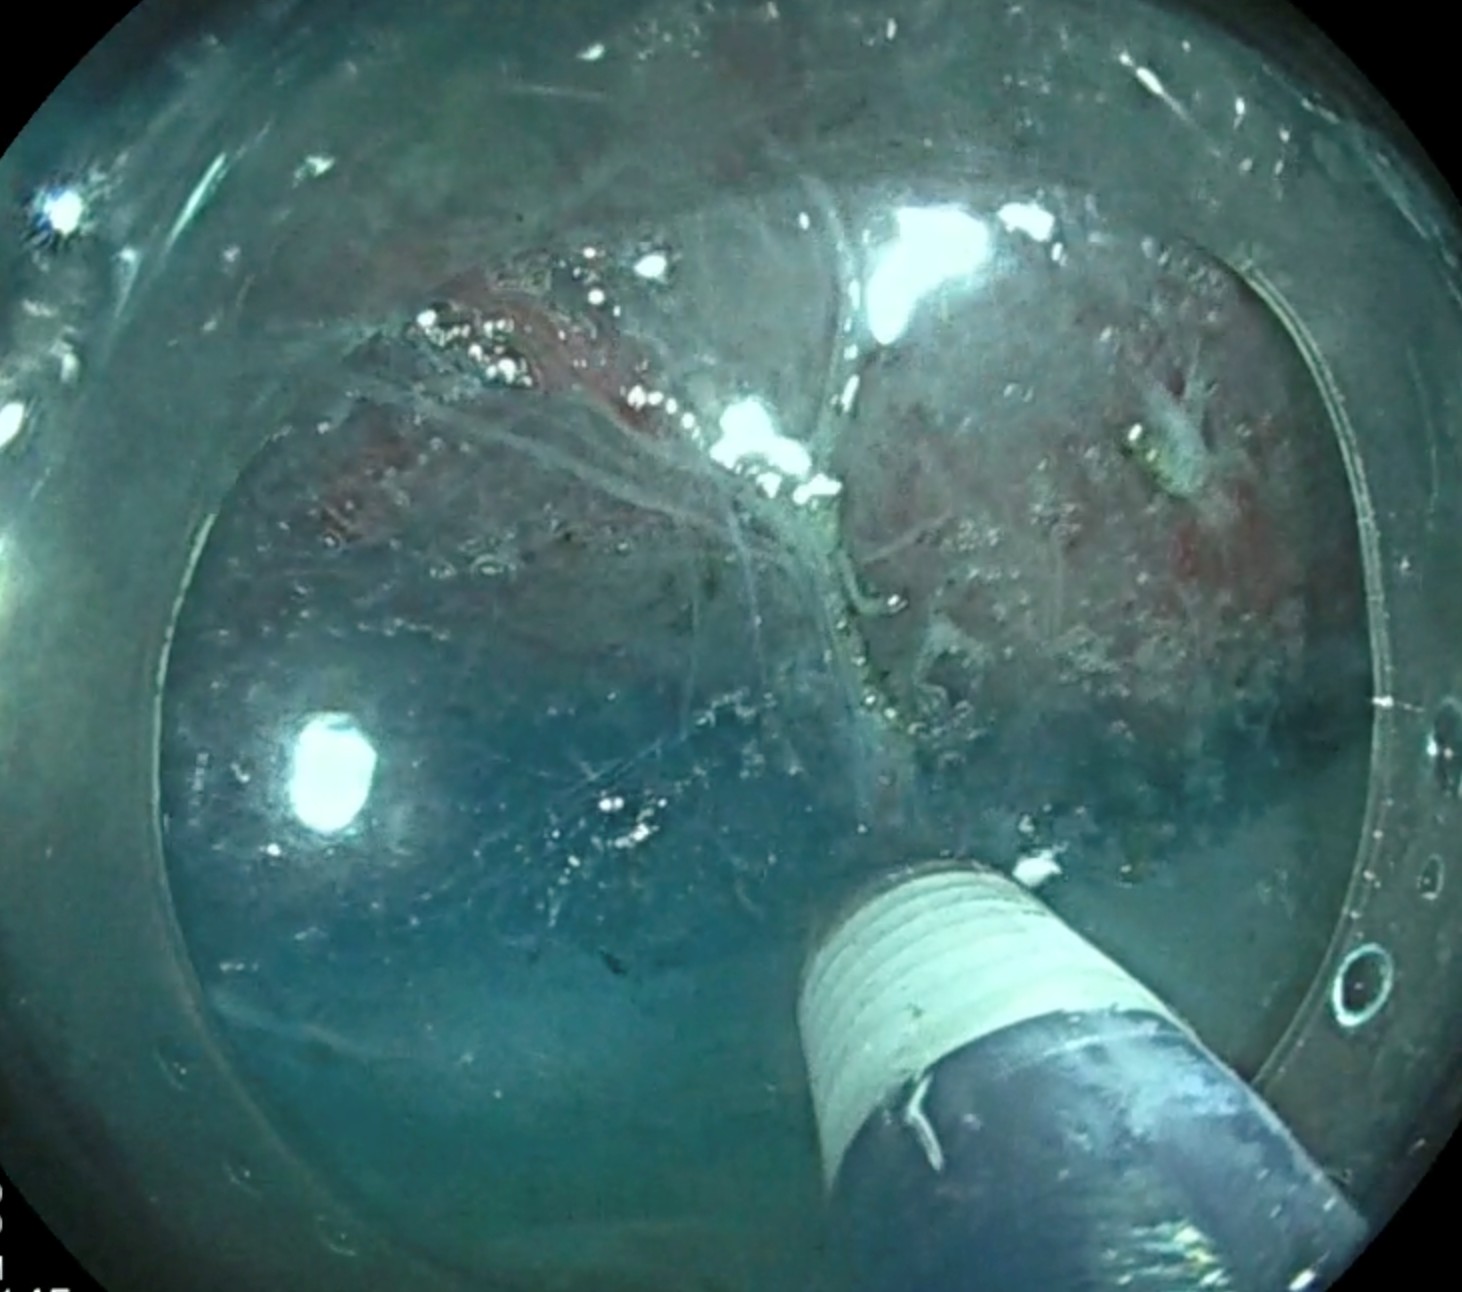

• L’intelligence artificielle (IA) s’implante aussi, avec des systèmes de prédiction du type histologique de polype (hyperplasique/adénome), mais aussi de détection assistée, signalant en temps réel les polypes à l’écran. Elle augmente ainsi le TDA, de 5 à 10 % en routine ; son bénéfice apparaît maximal chez les moins bons détecteurs. Par ailleurs, et en complément, les systèmes de coloration virtuelle d’augmentation du contraste et de zoom de l’image endoscopique permettront bientôt d’affirmer le diagnostic histologique du polype en temps réel, pour une meilleure aide à la décision (réséquer le polype ou le laisser en place).

Pour les lésions plus volumineuses (suspectes ou non de dégénérescence), la technique de dissection sous-muqueuse s’est imposée en France, leadeur dans les pays occidentaux. Son principe est de disséquer de façon minutieuse le plan sous-muqueux grâce à un couteau millimétrique, ce qui permet d’obtenir une résection monobloc quelle que soit la taille. Cette technique nécessite d’être réalisée par des opérateurs entraînés, après un programme d’apprentissage administré par la SFED, unique en Europe.